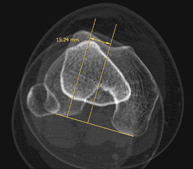

- TC Rodillas

Exploración radiológica que mediante un sistema de rayos X y detectores que giran alrededor del paciente, reconstruyendo las imágenes por ordenador (TC Multidetector), permite el estudio de huesos, músculos y articulaciones de la rodilla.

- TC Estudio rotacional EEII (Báscula Rotuliana, distancia TA-GT)

Exploración radiológica que mediante un sistema de rayos X y detectores que giran alrededor del paciente, reconstruyendo las imágenes por ordenador (TC Multidetector), permite calcular una serie de mediciones a nivel de caderas, rodillas y tobillos para solucionar problemas de rotación y angulación de las extremidades inferiores.